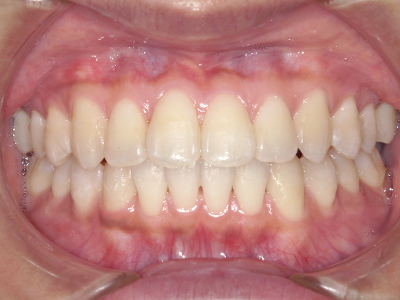

ないき歯科クリニックでは、これからあごが成長していくお子様や、歯並びが気になる成人の方など、さまざまな年代の方に対して矯正治療を行っています。

歯並びやかみ合わせを正しく整えると、笑顔や発音の自信につながり、むし歯・歯周病・口臭の予防にも役立ちます。

【4】矯正治療

矯正装置を装着し、調整しながら少しずつ歯を移動させ、歯並びを整えていきます。